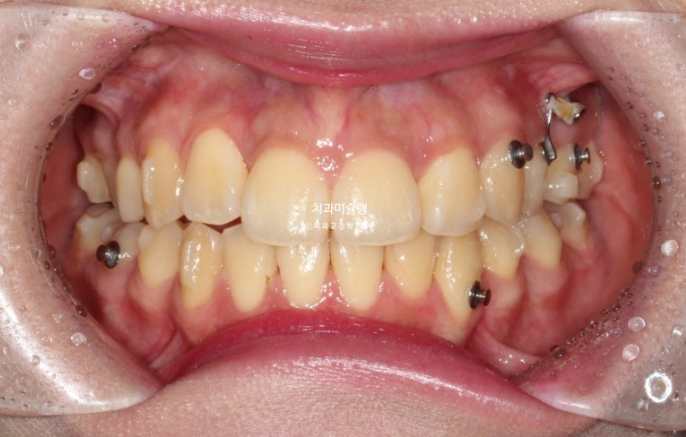

26.01

중심선은 일치하고

어금니 교합은 물샐틈 없는 1급 교합관계를 보이며 쫀쫀하죠 (?)

이제 전후 비교 보여드릴게요